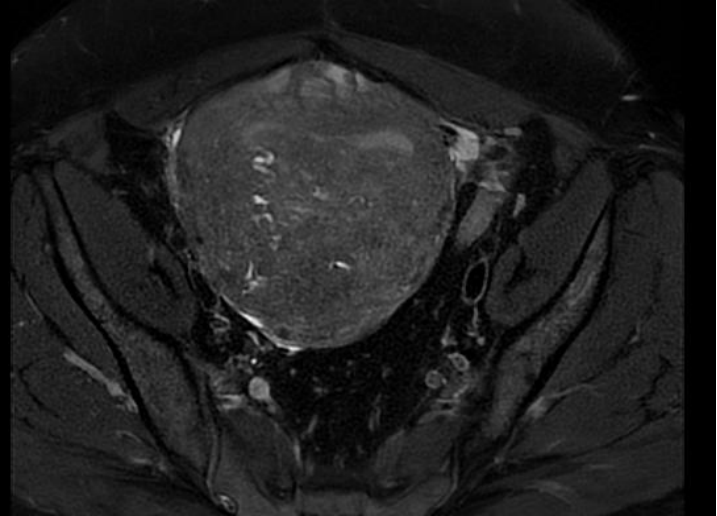

病史介绍 患者李女士,41岁,2024年11月21日就诊 主诉:进行性痛经伴月经增多10年 现病史:患者平素月经规律,月经周期28天-30天,经期7-9天,有痛经,近10年月经前3天痛经程度较重,且逐渐加重,持续4-5天,呈下腹坠痛,深部绞痛,末次月经疼痛VAS评分8分,口服布洛芬稍缓解;月经量逐步增多,经量多时每天需4片成人纸尿裤。8月余前外院放置曼月乐环后自行脱落。外院B超检查提示子宫后壁肌层内探及一不均回声区,大小约6.9cm*5.6cm*4.8cm。子宫局灶性腺肌症伴腺肌瘤形成。初步诊断“子宫腺肌症、剖宫产个人史”。 既往史:既往体健,否认慢性及传染性疾病,2018年行剖宫产术分娩,手术后恢复好。 月经史:13岁初潮,月经周期28天-30天,经期7天-9天,伴痛经(VAS评分8分),经量多,较多时每天需4片成人纸尿裤。 婚育史:已婚已育,1-0-0-1,既往剖宫产史。 家族史:否认家族中有遗传性疾病史。 体格检查:体重:59.2Kg,身高:160cm,BMI23.1,体温:36.6℃,脉搏:86次/分,呼吸:17次/分,血压:119/71mmHg,生命体征平稳,贫血貌,无痤疮,无多毛;乳腺未触及明显包块;余体检无殊。 妇科检查: 外阴、阴道无特殊,宫颈轻度柱状上皮外延,无举痛,子宫前位,子宫如孕3+月大,轻压痛,活动度偏差,质地硬,表面尚光滑,右侧附件区未及明显异常,左侧附件区有压痛略增厚,盆底未触及明显触痛结节。 辅助检查: 1、经阴道超声检查:子宫腺肌症伴腺肌瘤形成考虑,子宫前位,后壁肌层回声增粗,分布不均匀,范围约6.9cm*5.6cm*4.8cm,边界欠清,内见点条状血流信号;双层内膜厚度0.8cm,回声均匀;盆腔积液,后盆腔暗区1.6cm,透声好; 初步诊断: 1、子宫腺肌病; 2、子宫腺肌瘤; 3、轻度贫血; 4、剖宫产个人史。 诊断依据: 1、进行性痛经伴月经增多10年; ①经阴道超声检查:子宫腺肌症伴腺肌瘤形成考虑; ②CA 125:142.8↑U/ml; ③盆腔MRI平扫:子宫体积增大,子宫壁增厚,以子宫后壁为著,局部呈团块状,结合带增厚、边界显示不清,双侧卵巢大小欠对称,右侧较左侧稍饱满,约20mm*15mm。考虑子宫腺肌症伴腺肌瘤形成。 诊疗经过 诊疗思路:患者已婚已育,无再生育需求,根据病史、查体及辅助检查提示子宫腺肌病、子宫腺肌瘤,且病情较重,明显影响生活质量。 1.初次治疗分析与方案: 手术治疗:疼痛症状严重且月经过多,导致贫血,有手术指征。 药物治疗: (1)非甾体抗炎药,效果不佳,子宫腺肌病病理生理持续进展; (2)口服避孕药,患者年龄大于40岁,安全性下降、全身副作用增加; (3)GnRH-a,短期应用可行,长期应用受限; (4)孕激素(曼月乐脱落,不适合此患者;地诺孕素或地屈孕酮可行)经过和患者详细沟通病情,交待手术和药物治疗的利弊,患者知情,意愿先行药物治疗,选择药物治疗方案:地诺孕素2mg qd全周期口服。 2.第一次随访: 3.手术治疗: 行腹腔镜下子宫腺肌病灶切除术+腹腔镜子宫内膜异位病灶烧灼术+肠粘连松解术。 腹腔镜探查:部分肠系膜与腹壁粘连,子宫前位,增大如孕3+月,子宫后壁均匀增大,外凸明显;右侧输卵管及双侧卵巢外观未见异常,右侧输卵管伞端可见输卵管系膜囊肿大小约0.3cm。子宫表面可见散在紫蓝色内异结节,道格拉斯窝存在。探查余盆腹腔未见异常。下图所示分别为术前、术中、术后照片。 术后病理: 1、“子宫肿块”子宫腺肌症; 2、“左侧输卵管系膜囊肿”副中肾管囊肿。 术后处理:考虑患者术前使用地诺孕素有脱发副作用,患者无法接受。术后予地屈孕酮全周期治疗,服药方法:地屈孕酮20mg qd po治疗。 4.术后第一次随访: 5.术后第二次随访: 6.术后第三次随访: 1、本例患者就诊时年龄41岁,其临床症状主要以疼痛进行性加重,月经过多导致贫血,体检子宫明显增大,经阴道超声及盆腔磁共振提示:子宫腺肌症伴腺肌瘤形成考虑。CA 125:142.8↑U/ml。因此,临床诊断子宫腺肌病成立。治疗方案的选择根据临床症状、腺肌病灶大小的情况,选择手术治疗是较好的方案,但患者起初更希望药物治疗,交待病情及治疗风险后选择药物治疗,并且密切随访。 因子宫腺肌病雌激素依赖性,需要长期药物治疗,因此需有效安全且耐受性好的药物,持续使用到绝经。综合考虑后选择地诺孕素,随访后发现脱发明显,患者改选手术治疗,手术顺利。地屈孕酮对于异位病灶组织有显著抗增殖、促凋亡 2、手术治疗在子宫腺肌病治疗中的作用 全子宫切除的价值在于“一劳永逸”根治子宫腺肌病,然而子宫切除术不仅给妇女带来生理器官的缺失,可能造成卵巢功能减退、盆底功能障碍而影响患者的生活质量,而且可能造成心理伤害,尤其年轻或有生育要求的患者更是难以接受。 保留器官手术包括局灶性子宫腺肌病的子宫腺肌瘤剔除术、弥漫性子宫腺肌病病灶减少术等。其适应证为:有生育要求者、药物治疗失败希望保留子宫或对于药物治疗有禁忌证的患者。主要的手术原则包括:切除病变组织,尽量保留子宫肌层的强度和完整性,避免破坏子宫内膜腔,尽量减少浆膜损伤,保持输卵管的完整性,并对子宫肌层进行多层缝合[1]。对于保育患者尽量使用“冷器械”。 子宫腺肌病灶的切尽程度与术后病情密切相关,平衡病灶的去除程度、术中手术难度(如子宫创面的缝合、子宫重塑形)、术后恢复及子宫腺肌病病情的持续及远期复发、再妊娠患者的妊娠相关并发症是手术治疗及后续长期管理的难点。 3、子宫腺肌病病灶切除术后长期管理的意义 保留子宫手术后复发的预防子宫腺肌病保留子宫的手术后1年内复发率2.8%-14%,术后2年内复发率14.3%-49.0%[2]。子宫腺肌病术后需要长期管理,可以根据患者年龄、临床症状、有无生育要求、病变类型以及药物特点进行个体化治疗。本例患者术后管理方案为地屈孕酮20mg qd po全周期治疗,痛经及月经过多症状达到治愈效果。 术后长期管理是基于子宫腺肌病的多发性以及术后的高复发和迁延性,其术后管理的目的在于促进康复,减轻负担,降低并发症,提高生活质量。子宫腺肌病严重威胁女性健康,增加公共卫生负担。国内共识提出了子宫腺肌病的三级管理模式,实现全疾病周期的精准化和个体化管理,从而希望达到以下目标:预防其发生,延缓其进展,减轻其危害,防止其复发[3]。 参考文献: [1]Horng HC, Chen CH, Chen CY, Tsui KH, Liu WM, Wang PH, Chang WH, Huang BS, Sun HD, Chang TC, Chang WC, Yen MS. Uterine-sparing surgery for adenomyosis and / or adenomyoma. Taiwan J Obstet Gynecol. 2014;53(1):3-7.

4、盆腔MRI平扫:子宫体积增大,子宫壁增厚,以子宫后壁为著,局部呈团块状,结合带增厚、边界显示不清,TIWI呈等信号,T2WI呈低信号,其内可见局灶性高信号,DWI呈不均匀稍高信号,ADC呈等信号。双侧卵巢大小欠对称,右侧较左侧稍饱满,约20mm*15mm。盆腔内未见明显肿大的淋巴结。盆腔内少许积液。提示:子宫腺肌症伴腺肌瘤形成,必要时增强检查。所示双侧卵巢欠对称,右侧较左侧稍饱满,请结合临床、随诊。